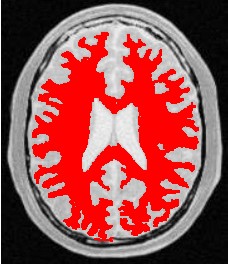

使用人体大脑截面图作为输入图像,选择合适的像素点作为种子像素,生长的结果如下图所示:

| 原始图像 | 连续阈值法 | 邻接连续阈值法 | 置信连接阈值法 |

| 参数 | [150,180] | [150,180] R:3 | Iter:10 factor:2.5 r:5 |

| 结果点数 | 15011 | 7854 | 14643 |